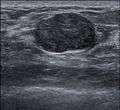

Fibroadenoma in ultrasound